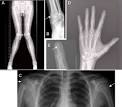

• En el tipo IA, llamado “osteodistrofia hereditaria de Albright”, hay estatura baja, cara redonda y huesos de la mano cortos. Causado por una mutación en el gen GNAS.

• Huesos de las manos y de los pies cortos (braquidactilia)

El diagnostico se hace con exámenes de sangre para medir el calcio total, fosfato y hormona paratiroidea en la sangre (calcio total corregido para albumina, < 8 mg/dl o calcio iónico < 4 mg/dl, junto con un fosfato > 5 mg/dl y niveles de hormona paratiroidea normal o aumentados). Otros exámenes son pruebas genéticas para saber si hay una mutación, exámenes de imágenes (rayos X de la mano, para ver los huesos cortos y si hay calcificaciones debajo de la piel (subcutáneas) y tomografía computadorizada del cráneo, para saber si hay calcificación de unas estructuras en el cerebro llamadas “ganglios de base” que son importantes para el movimiento de los músculos del cuerpo) y electroencefalograma, que puede ser anormal cuando el calcio está bajo.